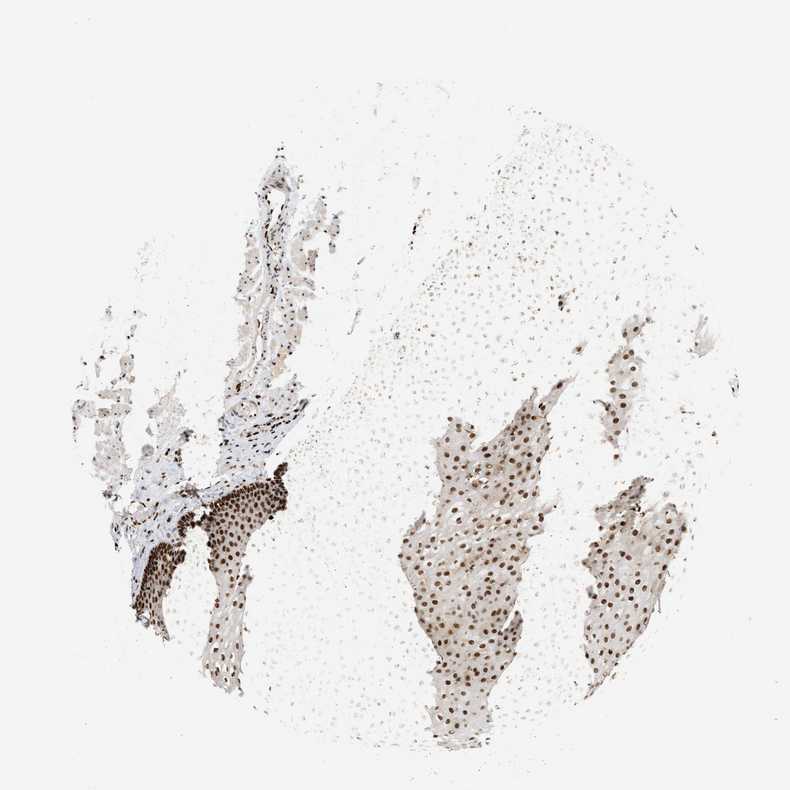

ESOPHAGUS - Antibody stainingi

Antibody staining in the annotated cell types in the current human tissue is reported as not detected, low, medium, or high, based on conventional immunohistochemistry profiling in selected tissues. This score is based on the combination of the staining intensity and fraction of stained cells.

Each image is clickable and will lead to virtual microscopy that enables deeper exploration of all samples and also displays staining intensity scores, fraction scores and subcellular localization as well as patient and tissue information for each sample.

Antibody HPA022961Antibody HPA024457

Squamous epithelial cells HighHigh